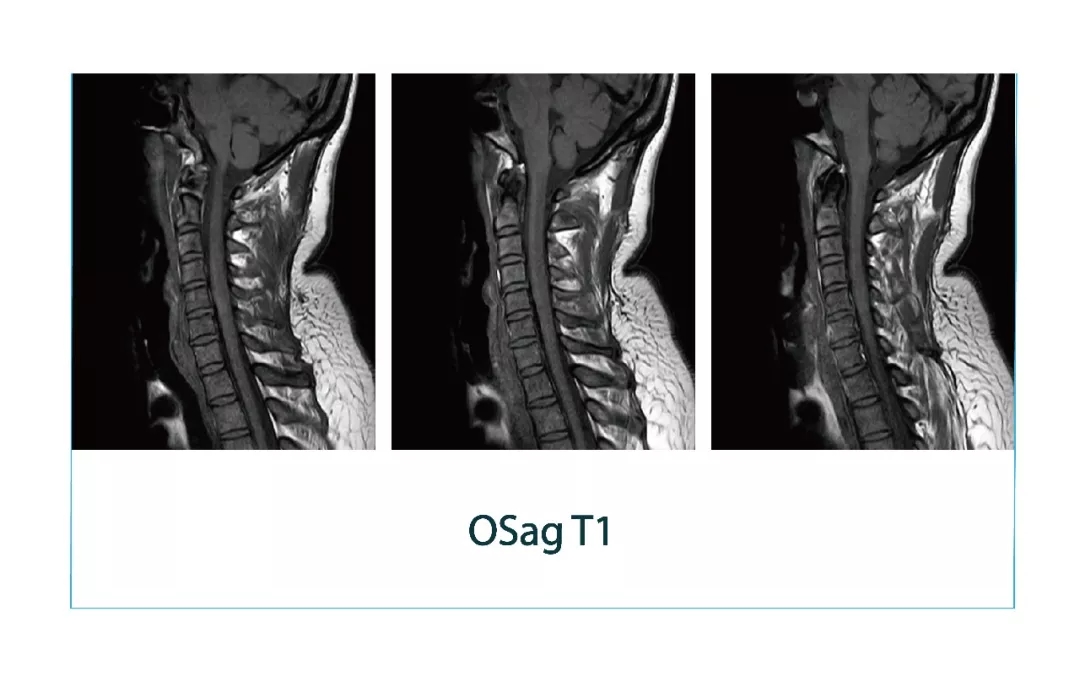

【朗润影像档案】20180330磁共振影像病例结果讨论